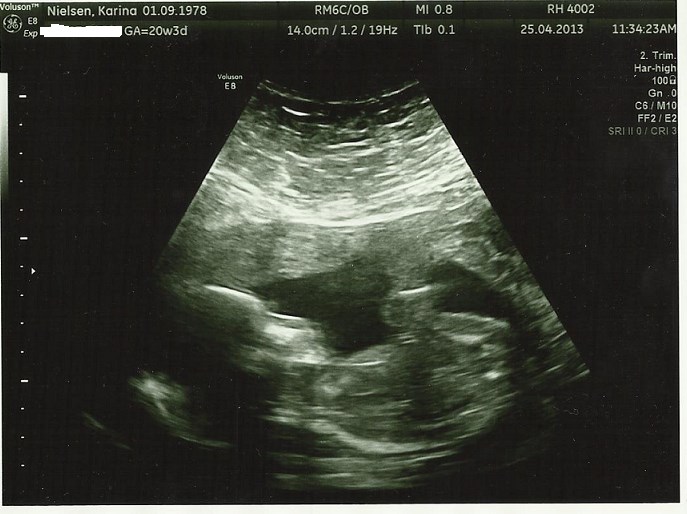

Vi har været afsted og se til lillefisen i dag 19+4 - 30. min hvor jeg var helt væk i skærmen, så jeg glemte helt at spørge om vægt osv.

Nå, det hele gik super fantastisk! En helt igennem sund og rask baby - lillefisen havde dog valgt ikke at ligge som scanningsdamen ville, men hun kom med et bud på et køn - en lillebror til Isabella

Haha prøv lige at se nogle aliensbilleder vi fik med hjem denne gang